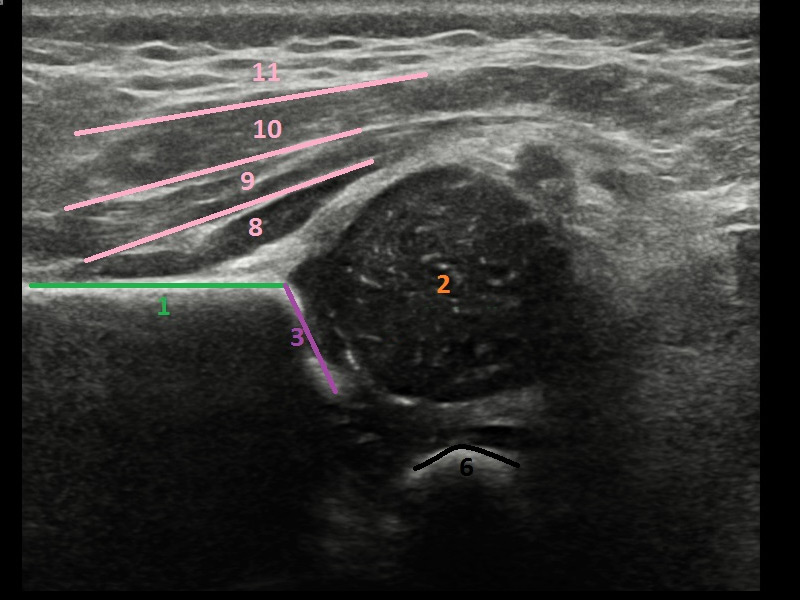

Mamarias

Es útil para observar algunos cambios en los senos, como masas (especialmente aquellas que se pueden palpar, pero que no se pueden ver en una mamografía) o cambios en mujeres con tejido mamario denso. También puede utilizarse para analizar un área que se observó en una mamografía y que causa sospecha. Es una de las pruebas más utilizadas para detectar el cáncer de mama.